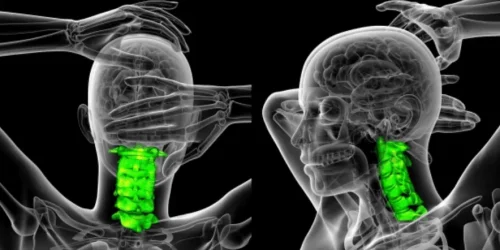

Meet and Understand Your Neck The neck is one of the most remarkable parts of your body – but it…